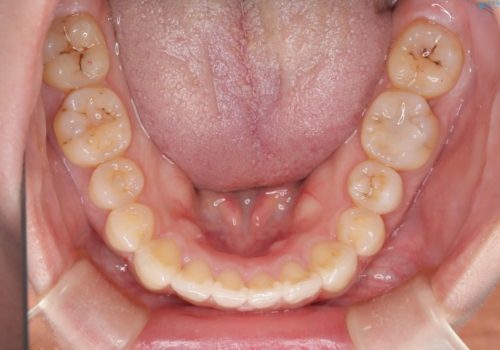

- 口元の突出感、歯のがたつきを主訴に来院された患者様です。非抜歯にて口元を下げるような治療計画を立案しました。非常に治療に対して真面目で協力的な患者様で、一緒に理想形を相談しながら治療を進めました。矯正前には、虫歯治療や親知らず抜歯を行っています。噛みしめ癖が強く、終盤は奥歯の噛み合わせのためにゴム掛けにご協力いただきました。